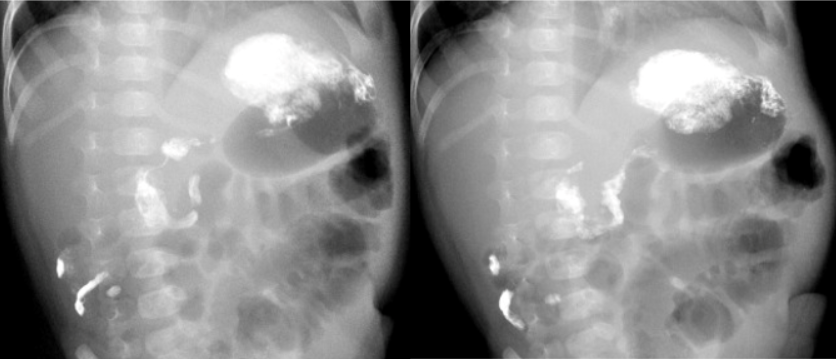

Рисунок 1 - Ребенок возрастом 2 месяца 10 дней, пассаж контрастного препарата

Примечание: рентгеноскопия, положение на спине с приподнятым на 45о правым боком, прослеживается С-петля двенадцатиперстной кишки; визуализируются остатки контраста после проведения ирригографии